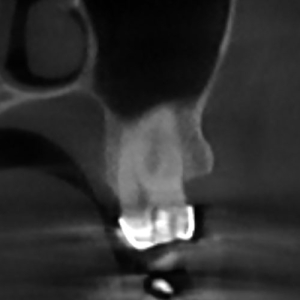

În urma iritațiilor cronice de lungă durată, precum cariile vechi netratate, pulpa dentară poate suferi modificări profunde, retrăgându-se sau transformându-se prin calcifiere. Aceste situații fac tratamentul endodontic mult mai complex.

Realizarea cavității de acces în dinții cu camere pulpare calcifiate (pietre pulpare) reprezintă o provocare majoră și, în absența magnificației optice (vizualizare mărită), poate duce la pierderi semnificative de structură dentară sănătoasă. De aceea, utilizarea tehnologiei moderne de mărire de până la 25 de ori, este necesară pentru un tratament precis, sigur și minim invaziv.

Furcațiile (ramificațiile) din profunzimea canalelor reprezintă o complexitate anatomică ce poate influența designul cavității de acces, în special la dinți precum premolarii mandibulari.

Prin utilizarea microscopului dentar operator, medicul poate realiza o cavitate de acces cât mai mică posibil, care permite un control superior al procedurii și păstrarea unei cantități maxime de structură dentară sănătoasă. Astfel, tratamentul endodontic atinge un echilibru optim între eficiența mecanică și respectarea principiilor biologice, pentru rezultate predictibile și durabile.